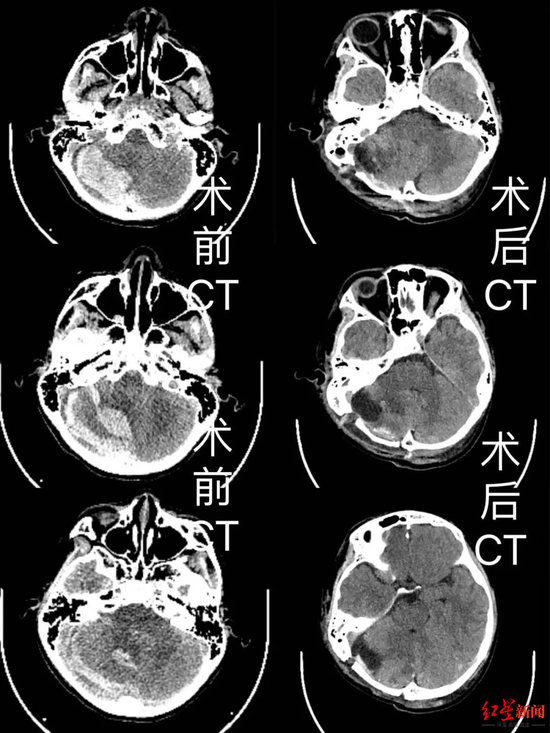

▲術前術后CT影像

▲術前術后CT影像情況緊急,劉嘉副主任醫(yī)師立即組織全科討論,在征得小迪父母同意后,決定為他安排手術治療。從急診兒科到神經(jīng)外科,再到麻醉手術中心和兒科重癥監(jiān)護室,市五醫(yī)院醫(yī)護人員們迅速為小迪搭建起一條生命通道。

手術室內,神經(jīng)外科手術團隊充分減少不必要的出血,保護幼稚嬌嫩的腦組織,歷時4個多小時,順利地清除了小迪腦內血腫并切除了畸形血管團,術后小迪被送到PICU(兒科重癥監(jiān)護室)密切監(jiān)護,并度過了遲發(fā)性出血、腦水腫和感染等一道道難關。